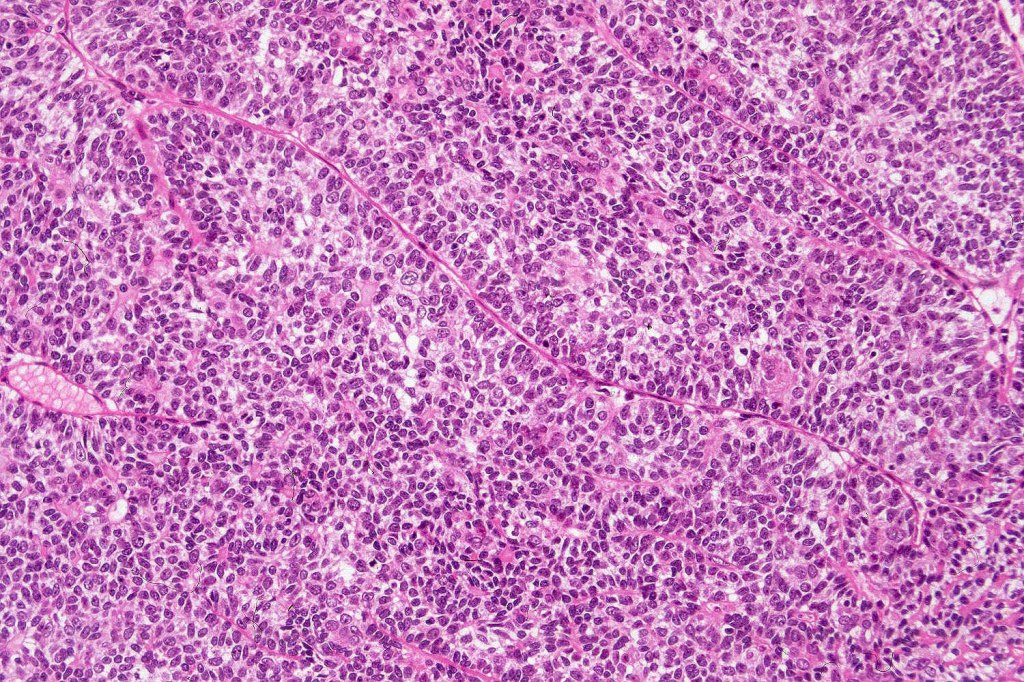

Histological features

•Pre-existent spiradenoma

•Malignant component shows loss of dual cell population, increased mitotic activity, atypical mitoses & necrosis

Classification

•1. Salivary gland type basal cell adenocarcinoma-like pattern, low grade (BCAC-LG)

•2. Salivary gland type basal cell adenocarcinoma-like pattern, high grade (BCAC-HG)

•3. Invasive adenocarcinoma, not otherwise specified (IAC-NOS)